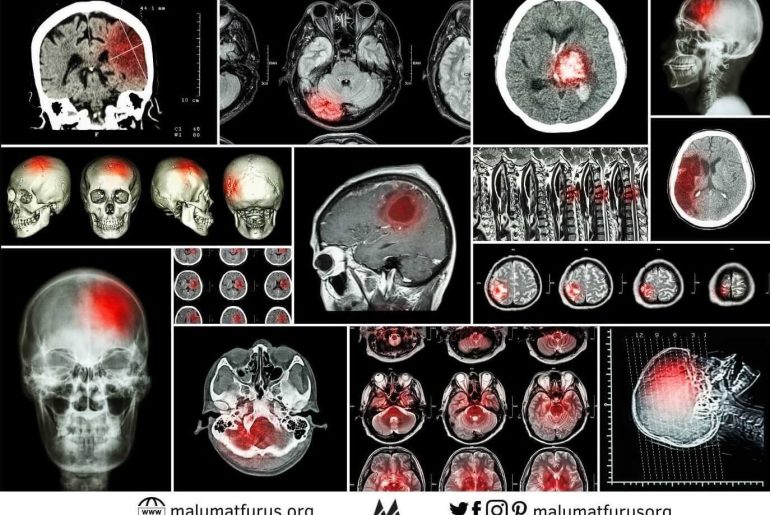

İnme Sözcüğünün İngilizce “Ischemic Neurologic Manifestation of Encephalon” Sözcüklerinin Baş Harflerinin Kısaltması Olduğu İddiası Doğru Değil Felç, nüzûl anlamlarına gelen…